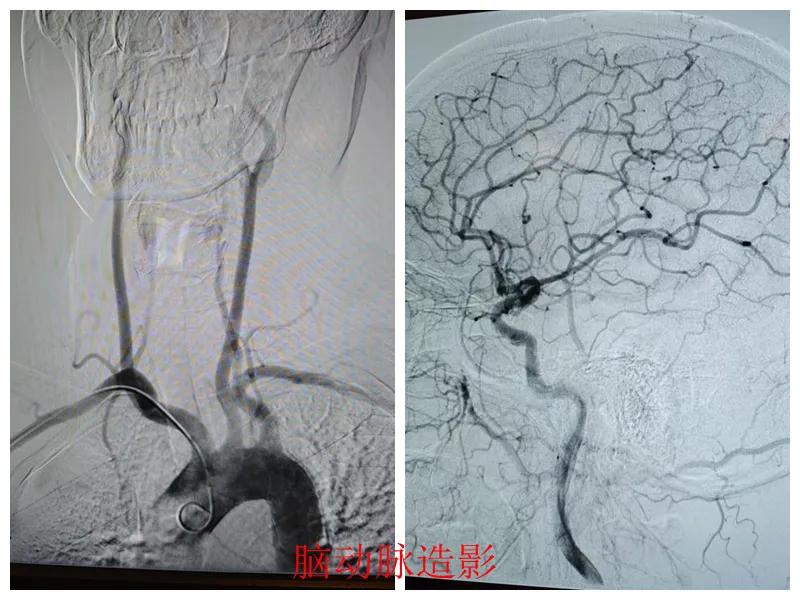

術前準備完善后,在王瑾院長帶領下,心血管內(nèi)科主任李慧新、影像科主任宋貴良、副主任醫(yī)師趙進科等緊密協(xié)作,成功為患者實施了冠狀動脈造影及腦動脈造影兩項檢查。冠狀動脈造影結果提示:患者右冠狀動脈慢性閉塞,腦動脈造影提示腦血管多支狹窄病變。